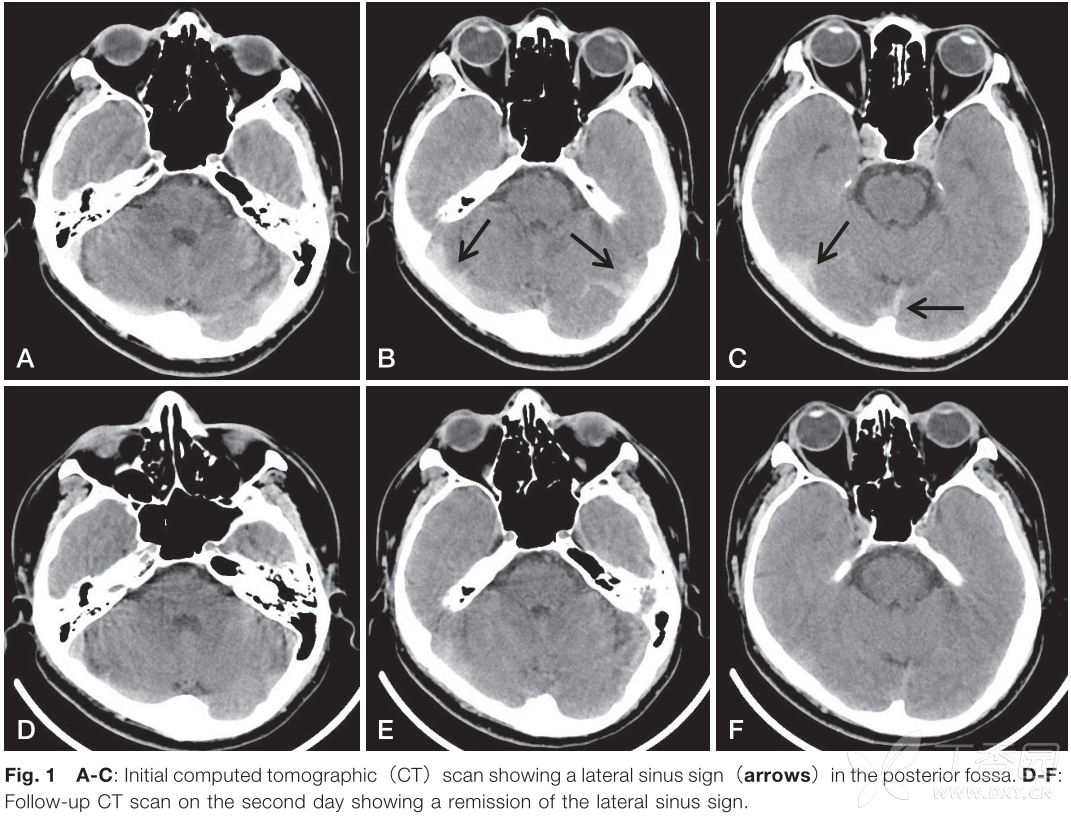

颅脑ct看到这个征像别忘记静脉窦血栓!

束带征和高密度三角征均为ct平扫征象,实质上都是由静脉(窦)内血栓呈